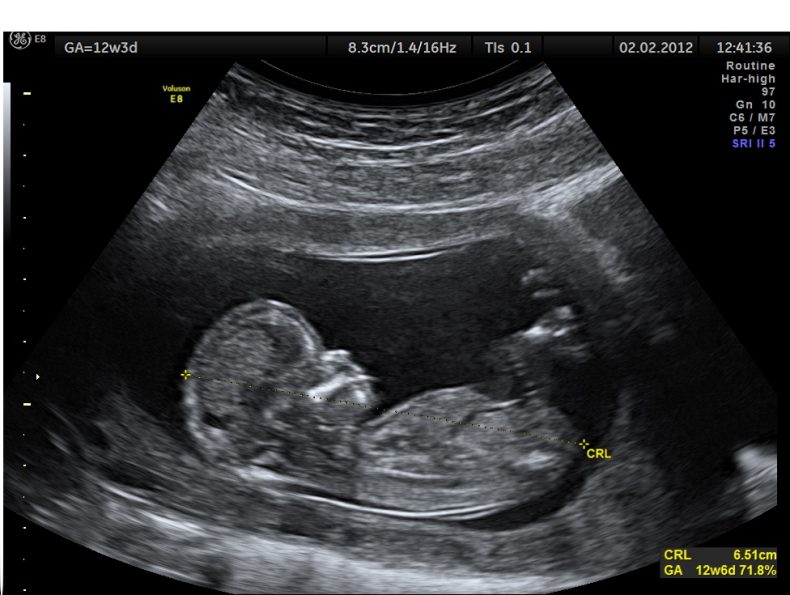

Por ejemplo, un manifiesto de Médicos por el Latido Fetal, que ha publicado la Fundación Más Vida. En el texto se constata que el feto tiene latido y que «este importante hecho sin duda constituye una parte fundamental de las que se deben considerar a la hora de plantearse la denominada Interrupción Legal del Embarazo (ILE): el embrión-feto tiene latido».